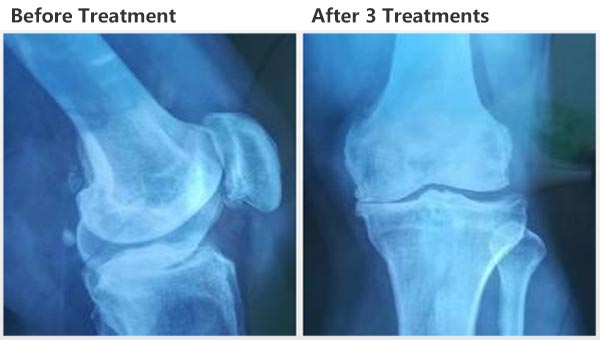

Clinical Effect